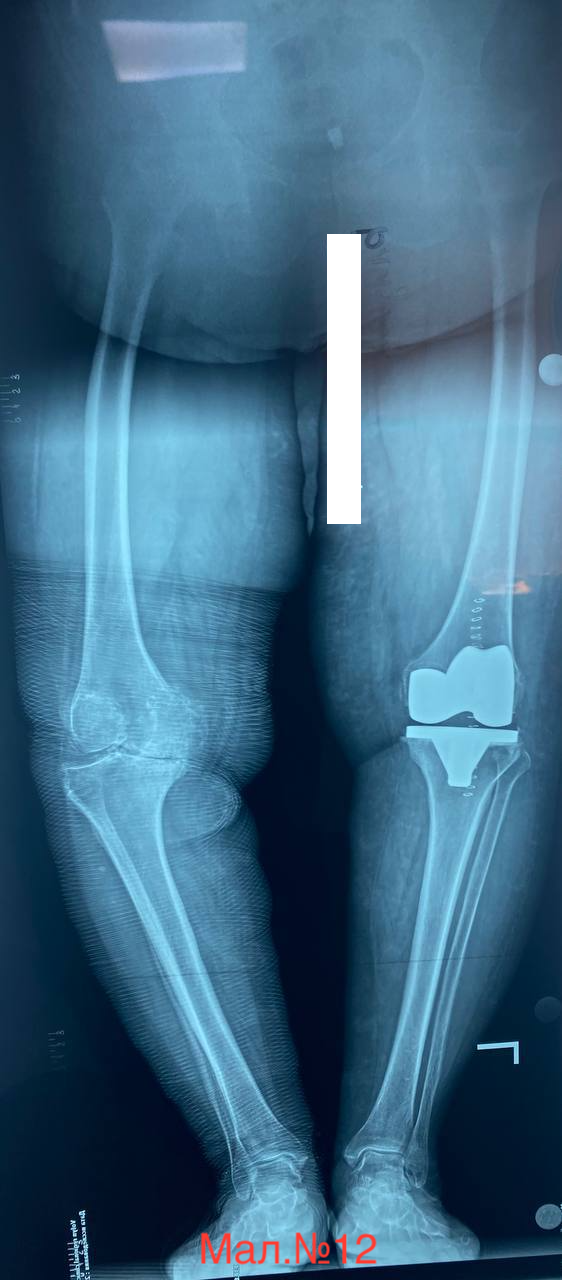

photo_2023-12-13 17.11.23